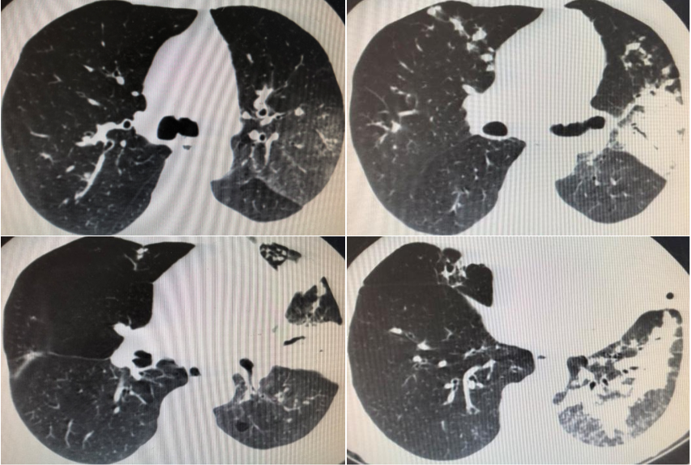

胸部CT(2019-02-11)(图1)。

前后两次胸部CT对比(2019年2月11日与2月20日),治疗后的胸部CT显示在原有部位上实变进一步加重,结合该患者全身炎症反应综合征存在,是否可应用小剂量全身激素?